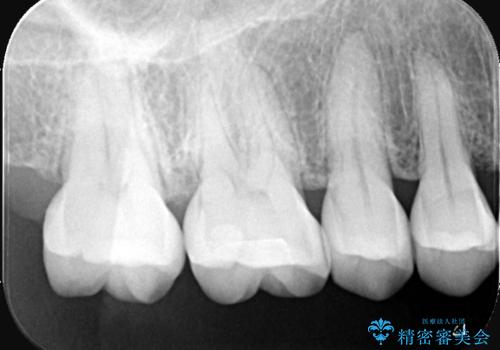

- 主訴:奥歯の噛む面が虫歯になっている。プラスチックの材料で治療可能と言われたが、劣化してまた虫歯になるのが怖いのでセラミックの詰め物にしたい。

咬合面にう蝕があり、CR修復・各種インレーの特徴を説明し、審美性・適合性の良いセラミックインレーでのやり替えとなりました。

咬合面のみのう蝕の場合CR(コンポジットレジン)修復を行うことが多いですが、CRは経年劣化しやすく二次う蝕の可能性を帯びています。それに比べセラミックは着色や収縮が少なく、経年劣化しにくい材料のため、今回はセラミックインレーでの治療となりました。